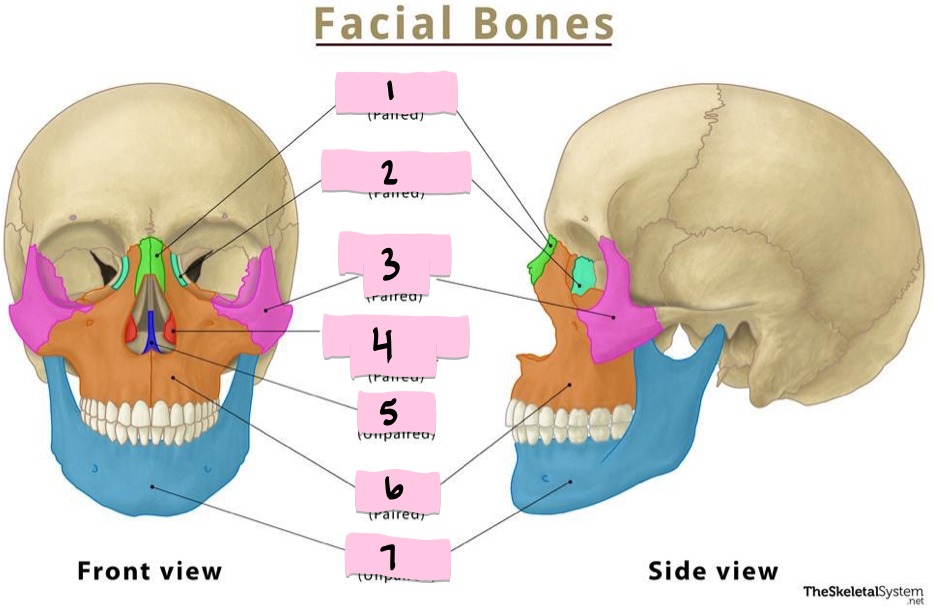

What is 1 pointing to?

Nasal bone

What is 2 pointing to?

Lacrimal bone

What is 3 pointing to?

Zygomatic bone

What is 4 pointing to?

Inferior nasal conchae

What is 5 pointing to?

Vomer

What is 6 pointing to?

Maxilla

What is 7 pointing to?

Mandible